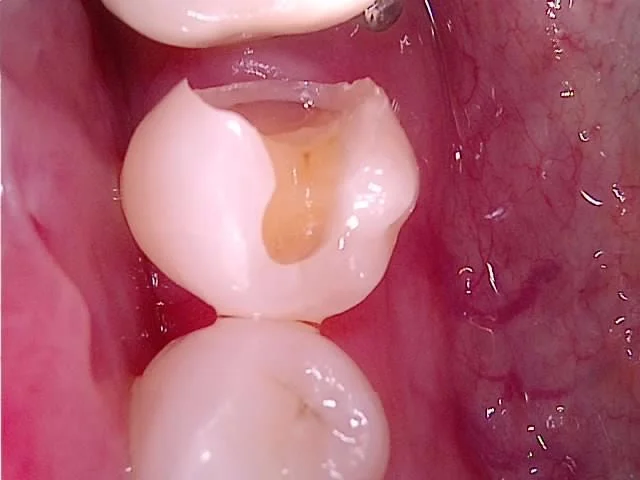

치아를 삭제하다 보면 충치가 발견되고 이렇게 기록으로 남겨놓습니다!

본 채득 후 임시 재료로 매운 모습

치아를 다듬은 후 본을 채득하고 임시 재료로 매웁니다! 일주일 후 접착하면 끝!